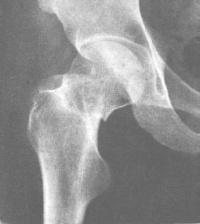

按股骨颈骨折部的形态分为嵌入型和错位型骨折。这两型股骨颈骨折的骨折线可表现为致密线和/或透亮线。致密骨折线表示两骨折端的骨小梁有重叠嵌插,而透亮骨折线则意味着两骨折端有分离。

嵌入型股骨颈骨折无明显错位,通常股骨颈可见模糊的致密骨折线,局部骨小梁中断,局部骨皮质出现小的成角或凹陷,股骨干的外旋畸形小明显。此型骨折属较稳定性骨折。由于骨折发生时外力作用的不同,股骨头可发生不同程度的内收、外旋。前倾或后倾的成角畸形。如出现嵌入端成角畸形较明显,或骨折线的斜度较大、骨折端部分有分离,或股骨干外旋明显时,提示骨折不稳定。

错位型股骨颈骨折较常见,亦称为内收型股骨颈骨折。两折端出现旋转和错位。股骨头向后倾骨折端向前成角,股骨干外旋向上错位,骨折线分离明显。

另外,接骨折部位又可分型为:头下型:骨折线位于头颈交界处;经颈型:骨折线位于股骨颈的中段;基底型:骨折线位于股骨颈底部,大部分位于关节囊外;头颈型:骨折线上端在头下,下端在股骨颈的中部,此型骨折近端的血供不好,不易愈合。